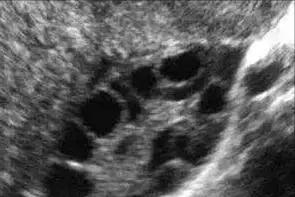

平时看门诊的时候常常有病人会问我,医生,为什么你要给我在月经期做阴道B超检查呢?经期不是不能做检查的吗?每当这个时候,我都会耐心地跟她解释,月经期第二至第四天的经阴道超声检查的目的,是为了测量双侧卵巢直径2~10 mm的小卵泡(也叫窦卵泡)的数目,这是一项评估卵巢储备功能的重要而且比较可靠的检查方法。那么什么是卵巢储备功能,它有什么重要的意义呢?

卵巢储备功能是指卵巢皮质区内的卵泡生长、发育形成可受精卵子的能力,包括卵巢内存留卵泡的数量和质量,它反应了女性的生育潜能。卵巢储备功能不良是指卵巢内存留的可募集卵泡数目减少,卵母细胞质量下降,可导致生育能力降低或出现过早绝经倾向。一般女性在出生时体内大约有 200 万个原始卵泡,到初次月经的时候只剩下 20 万~ 30 万个,自此之后,每个月会减少几百个,一生中大概只有400~500个卵泡能够发育成熟并排卵,随着女性年龄的增长,卵巢内卵泡数量越来越少,直到绝经后卵巢萎缩。目前由于外界不良环境的不断刺激、基因突变或染色体变异的不断增加、卵巢手术、肿瘤放疗及化疗、心理因素等的影响,卵巢储备功能不良有逐渐增多及年轻化的趋势。那么除了经期阴道超声检查卵巢窦卵泡这一评估卵巢储备功能的最佳单一指标外,还有什么其他的指标呢?